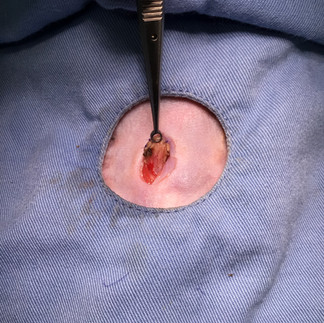

また子宮頸部に腫瘤が嵌まっており、子宮角をそれぞれ切除した後に子宮頸部の内側から腫瘤のみを取り出す核出術を行い、出血がないことを確認して閉創しました。

病理診断:子宮頸部の平滑筋腫

子宮頚部腫瘤では平滑筋に由来する腫瘍が観察された。

核の大小不同など中程度の異型性を示す腫瘍細胞もみられますが、増殖活性や浸潤性は乏しく、良性と判断する。